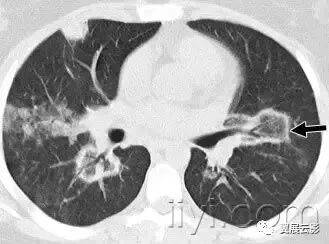

四十五、机化性肺炎

病理:机化性肺炎的组织病理学特征是松散的结缔组织位于气腔和远端气道内。间质的炎症或者纤维化很轻,或者没有。原因不明性机化性肺炎是特发性间质性肺炎中比较特殊的一类。但是在多种情况下均可见机化性肺炎的组织病理学模式,包括肺感染,高反应性肺炎,胶原血管病。

平片和CT:在平片和CT上,机化性肺炎最主要的特征是含气腔隙的实变,在原因不明性间质性肺炎中,病变部位特征是胸膜下和基底段,有时候微软支气管。机化性肺炎的其它表现包括磨玻璃影,树芽征和结节影。